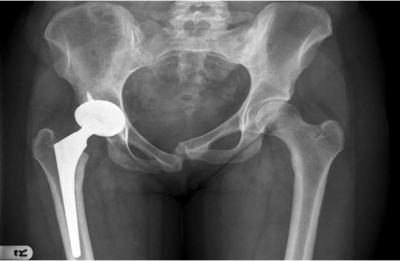

耻骨联合分离症是指骨盆前方两侧耻骨纤维软骨联合处,因外力而发生微小的错移,表现耻骨联合距离增宽或上下错动出现局部疼痛和下肢抬举困难等功能障碍的软组织损伤性疾病。

耻骨联合分离示意图